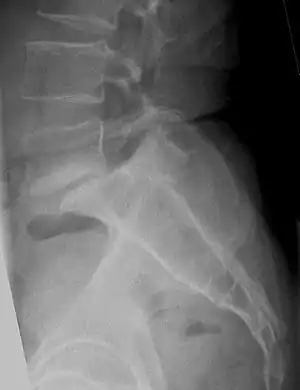

| یک تصویر پرتو ایکس از ستون فقرات جانبی کمری دچار به لغزش درجه سه مهره پنجم کمر بر روی مهره خاجی. | |

لغزش مهره چهار درجه دارد. درجه چهار شدیدترین حالت میباشد و نیاز به عمل جراحی دارد. شایعترین حالت لیزخوردگی در ستون فقرات، حرکت مهره پنجم کمر(L5) بر روی مهره خاجی یا ساکروم (S1) میباشد. عواملی چون فشار شدید، شکستگیها، تومورها، برخی از عوامل مادرزادی یا تغییرات تخریبی در ناحیه پشتی مهرهها میتوانند باعث بروز این حالت شوند. لیزخوردگیها به خصوص درجات شدید آن باعث فشار به عناصر عصبی نخاع میگردند. درجات پایین لیزخوردگی به درمان محافظهکارانه[2] جواب میدهد و فیزیوتراپی در این زمینه مؤثر است. انجام تمریناتی که باعث افزایش ثبات ستون فقرات میگردند و تحت عنوان تمرینات ثباتدهنده[3] معروف اند با توجه به وضعیت بیماربسیار کمککننده میباشند. هدف اصلی از انجام این گونه تمرینات، تقویت عضلات عمقی ستون فقرات میباشد که نوع تمرینات و شدت آن از طریق فیزیوتراپیست کنترل میشود.